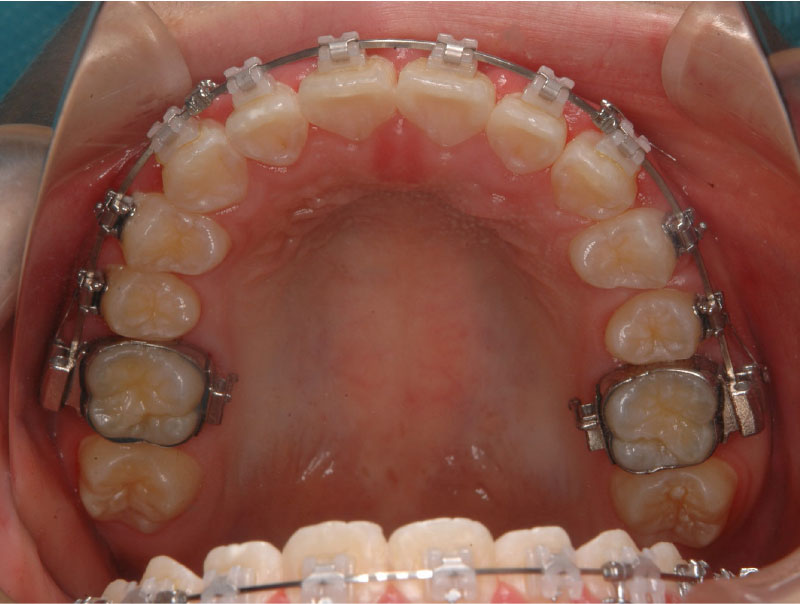

2、バンドフォーミング

奥歯にバンドを作りワイヤーを通します。

必要に応じてTAD(Temporary Anchorage Device)を使用する場合があります。TADとはミニスクリューを用いた矯正治療で前歯を後ろに下げたり、奥歯のコントロールをする際にTADを固定源にして歯を引っ張る装置です。

3、インダイレクトボンディング

当院では、インダイレクトボンディング法 (間接接着法)を取り入れています。

インダイレクトボンディング法とは、ブラケット(ワイヤーを通すために歯に装着する装置)を模型上に正確に位置づけし、専用のトレーを用いて装着する方法です。

当院では、目立ちにくいセラミックのブラケットを使用しています。